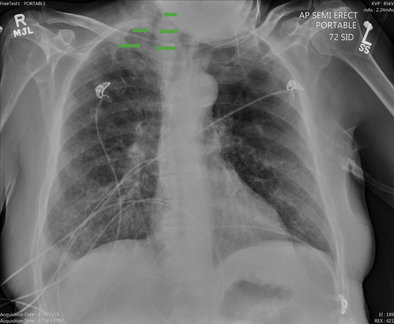

La sintomatologia del paziente è peggiorata rapidamente tanto che hanno provveduto ad un intubazione d'urgenza. Successivamente gli esami hanno mostrato la causa di quel peggioramento critico nelle ecografie e radiografia, sotto.